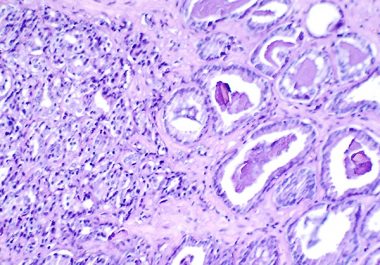

The combination of ipilimumab and nivolumab was approved by the FDA for metastatic colorectal cancer that is positive for...